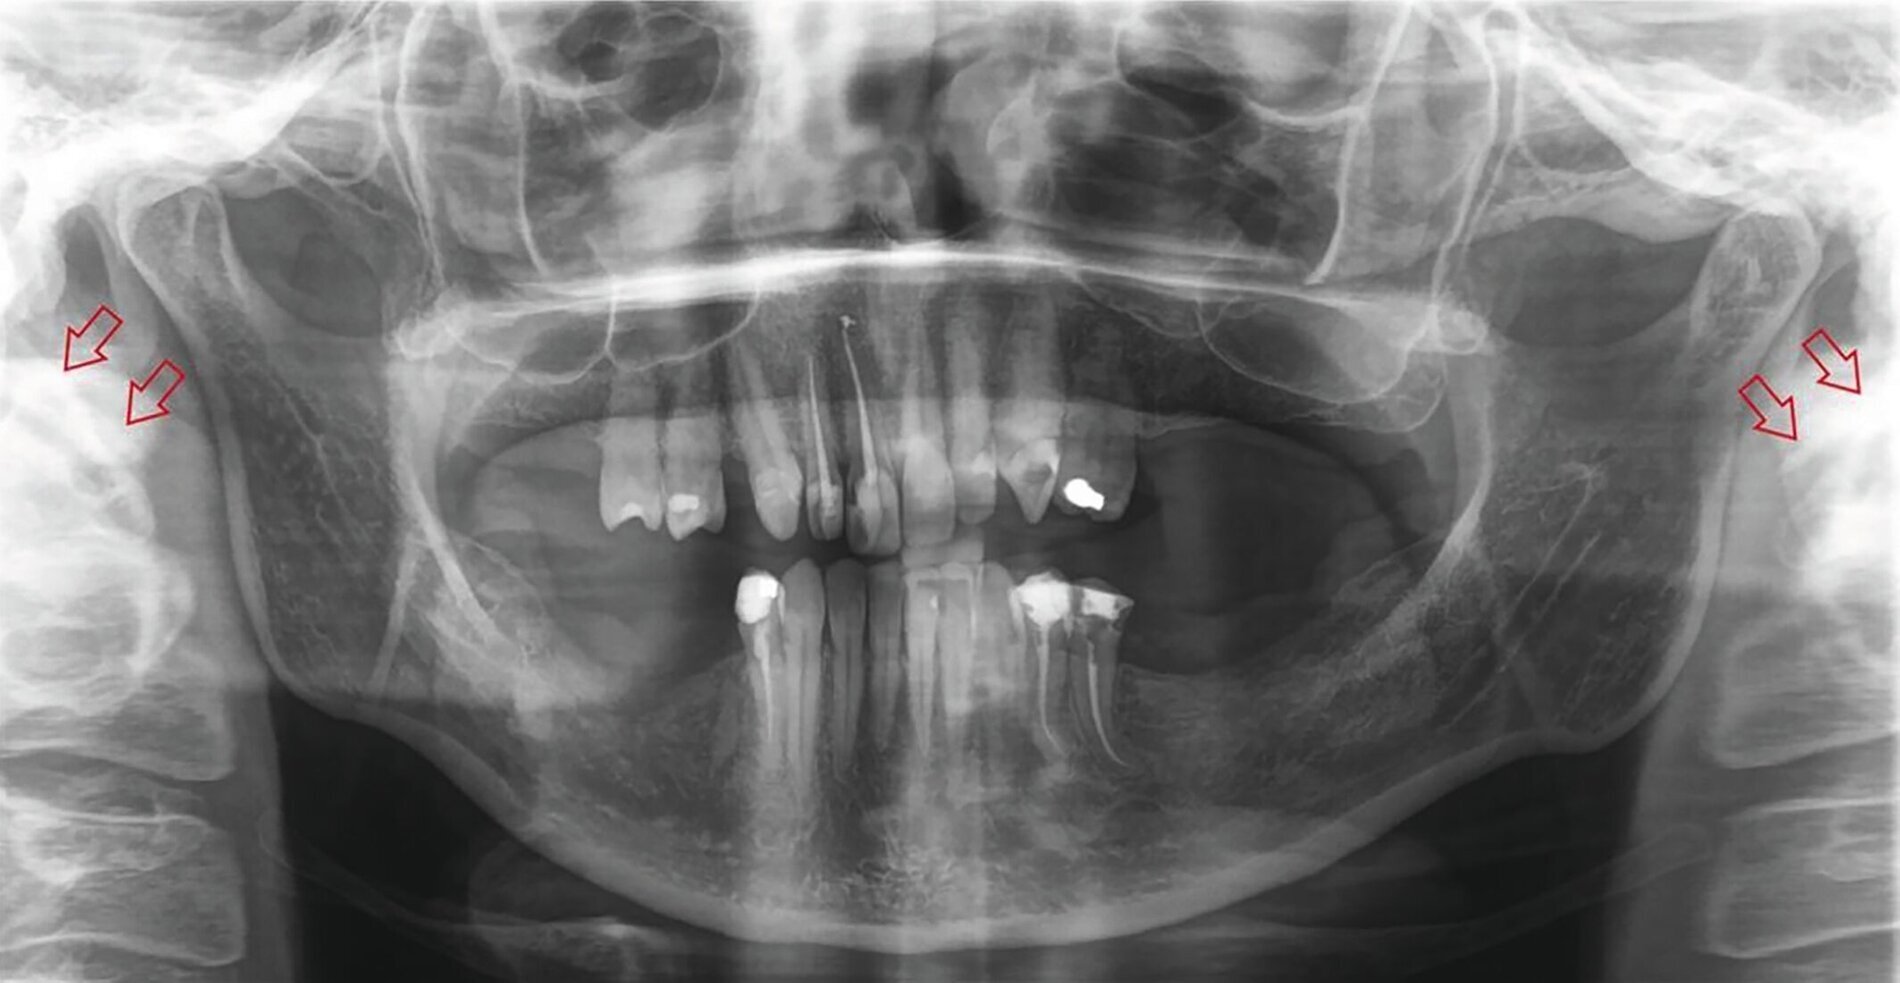

Here is also a Case report from their Department (with webpage translation to english ):